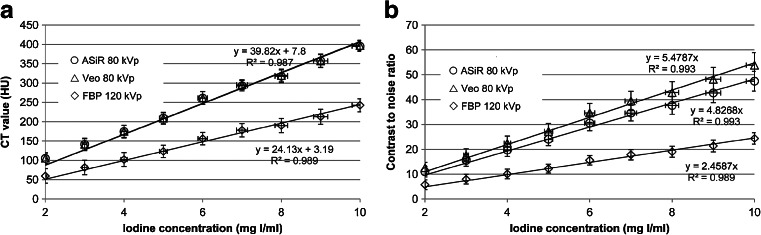

CT values showed a linear response as a function of iodine concentration (Fig. 1) and there was no significant difference between reconstruction methods (Pearson correlation 1.00, p < 0.001). Lower kVp resulted in higher CT values (1.65-fold) as demonstrated by the increased slope of the curve. At 80 kVp the iodine concentration fraction that results in equal CT value compared to 120 kVp is about 60 %. The CNR increases more rapidly, caused by the combined effect of higher CT values and noise reduction due to both IR algorithms. At 80 kVp, the iodine concentration fraction that results in equal CNR compared to 120 kVp–FBP is about 50 % when using ASiR and about 45 % when using Veo.

Fig. 1.

Mean CT value (a) and contrast to noise ratio (b) as a function of iodine concentration for FBP at 120 kVp and both ASiR and Veo at 80 kVp, obtained from phantom data. Error bars represent 95 % confidence intervals